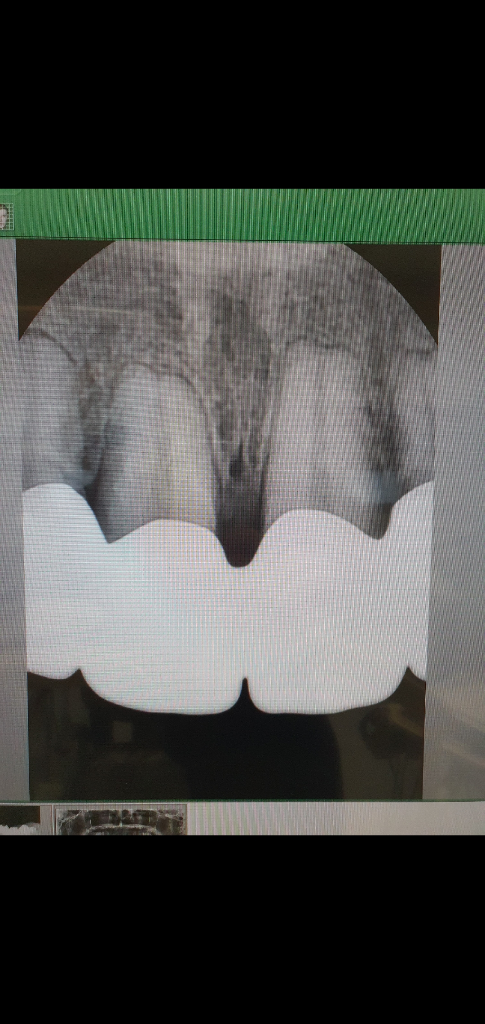

치근단 사진은 7월 7일에 찍은겁니다.

이렇게 아침에..저리 이사이 에 염증이 있습니다.